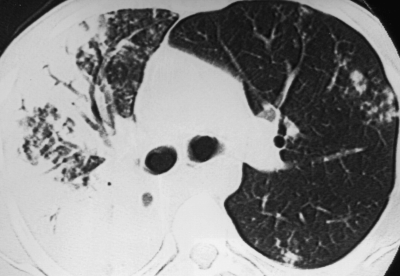

Преобладающий рентгенологический синдром диссеминированного туберкулёза лёгких - очаговая диссеминация. Для гематогенной и лимфогематогенной диссеминации характерны множественные очаговые тени, которые расположены в обоих лёгких относительно симметрично. При лимфогенной диссеминации очаговые тени часто определяются в одном лёгком, преимущественно в средних отделах (рис. 18-23). Двусторонняя лимфогенная диссеминация обычно бывает асимметричной.

Рис. 18-23. Туберкулёзная диссеминация в лёгких. а - гематогенная; б - лифогенная; в - бронхогенная.